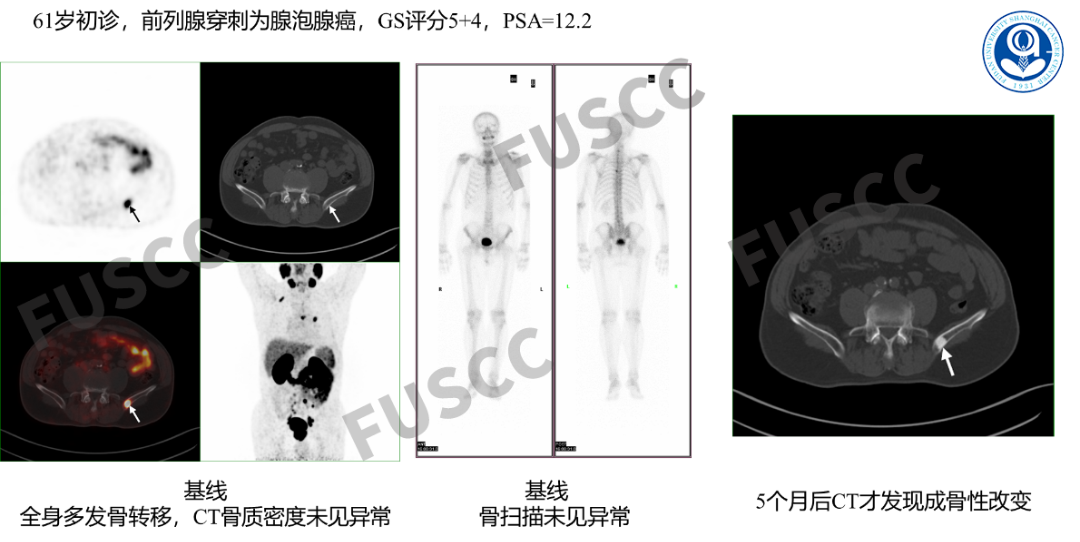

初始分期

对于中高危前列腺癌患者推荐PSMA检查进行精准的临床分期。